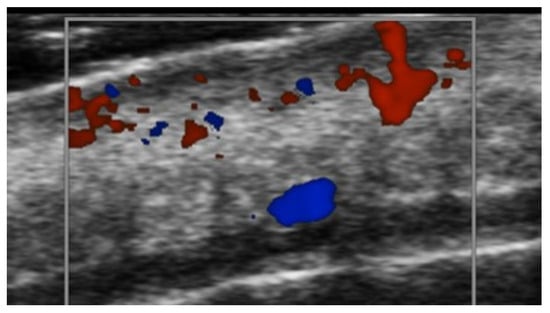

- Di Battista, M.; Vitali, S.; Barsotti, S.; Granieri, G.; Aringhieri, G.; Morganti, R.; Dini, V.; Della Rossa, A.; Romanelli, M.; Neri, E.; et al. Ultra-high frequency ultrasound for digital arteries: Improving the characterization of vasculopathy in systemic sclerosis. Semin. Arthritis Rheum. 2022, 57, 152105. [Google Scholar] [CrossRef] [PubMed]